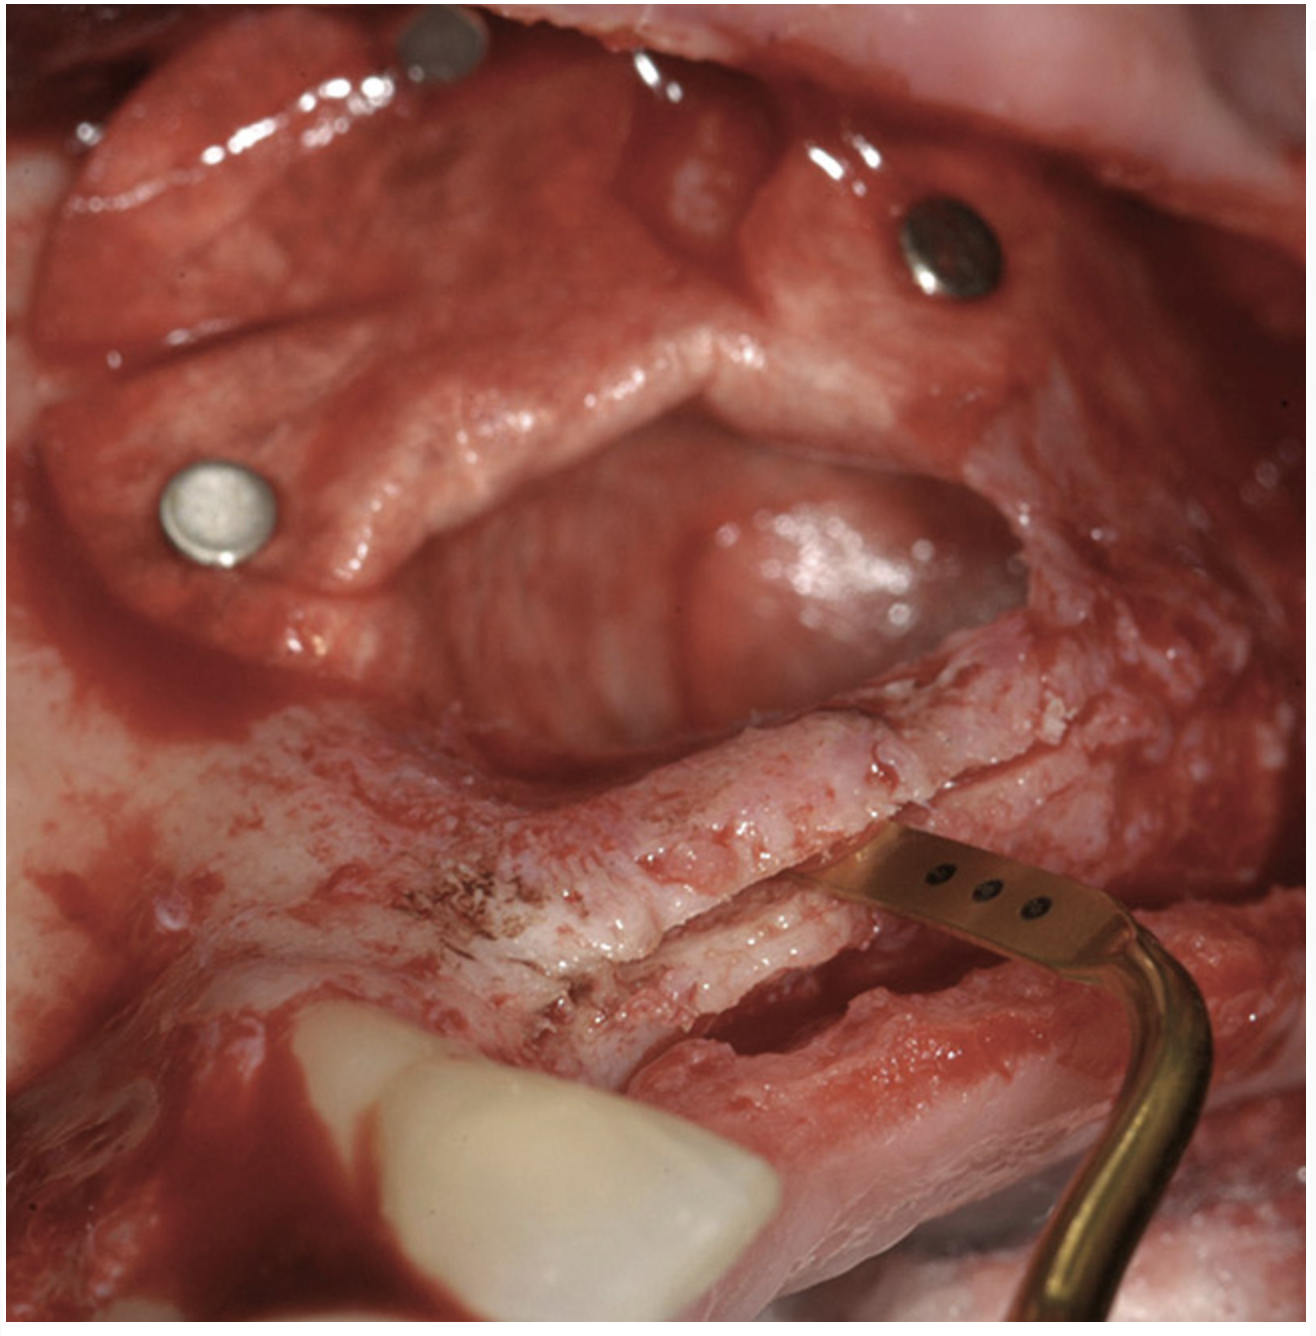

Figure 18  Three months after implant placement, but before soft-tissue vestibuloplasty.

Figure 18

A 62-year-old woman was referred for fixed tooth replacement of the missing maxillary left cuspid, bicuspids, and first molar (Figure 11). Clinical and CBCT evaluation revealed an almost fully pneumatized maxillary left sinus along with alveolar width deficiency. The treatment plan called for a four-unit, implant-supported splinted fixed bridge. A left sinus augmentation along with a ridge split and interpositional bone graft consisting of rhBMP-2/ACS (INFUSE Bone Graft) and mineralized allograft (MinerOss) covered by a dense porous polyethylene mesh (Medpor®, Stryker, www.stryker.com) were done simultaneously (Figure 12, Figure 13 and Figure 14). Six months later, a follow-up CBCT revealed a well-incorporated graft with adequate bone volume and density for implant placement (Figure 15 and Figure 16). Final bridge fabrication followed 3 months later (Figure 17 and Figure 18).